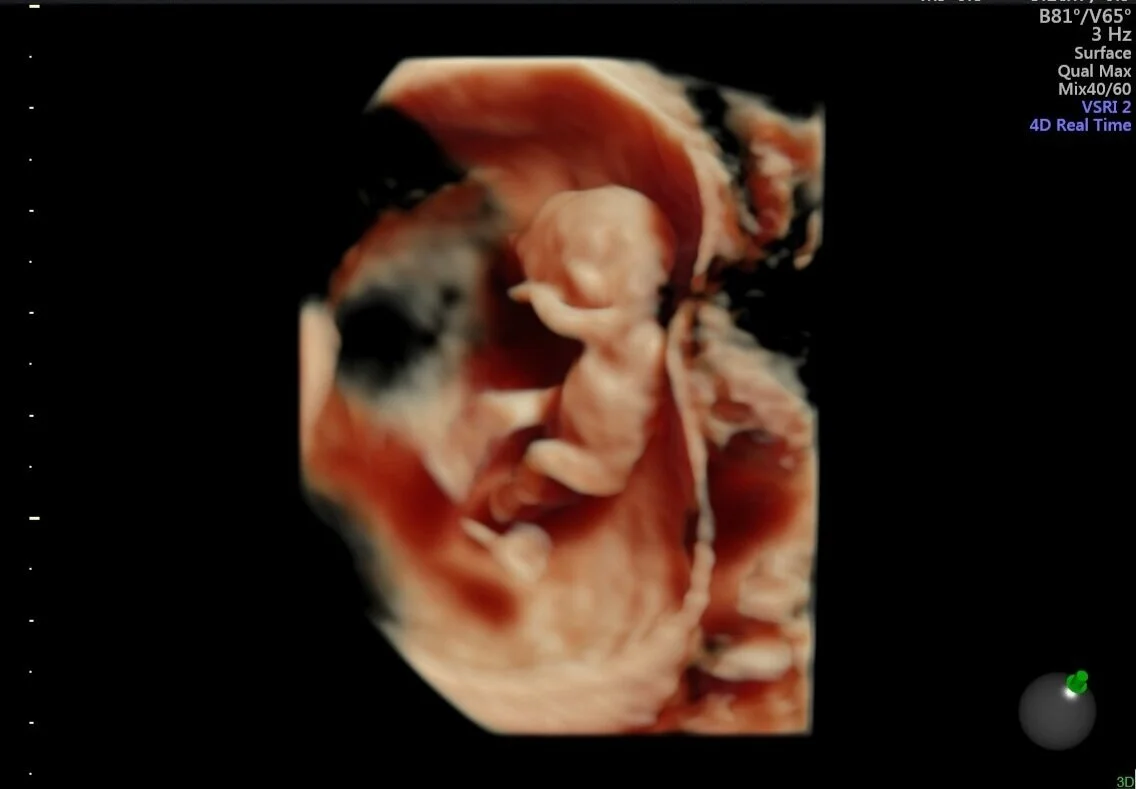

Desenvolvimento Do Bebe Na Barriga Video Impressionante Mostra Imagens Em 3d Vix

O Desenvolvimento Do Bebe Dentro Da Barriga Em Apenas 4 Minutos Video 3d

Ultra Sonografia 3d E 4d Evolucao Do Bebe Na Barriga Youtube

O Desenvolvimento Do Bebe Lfginecologia